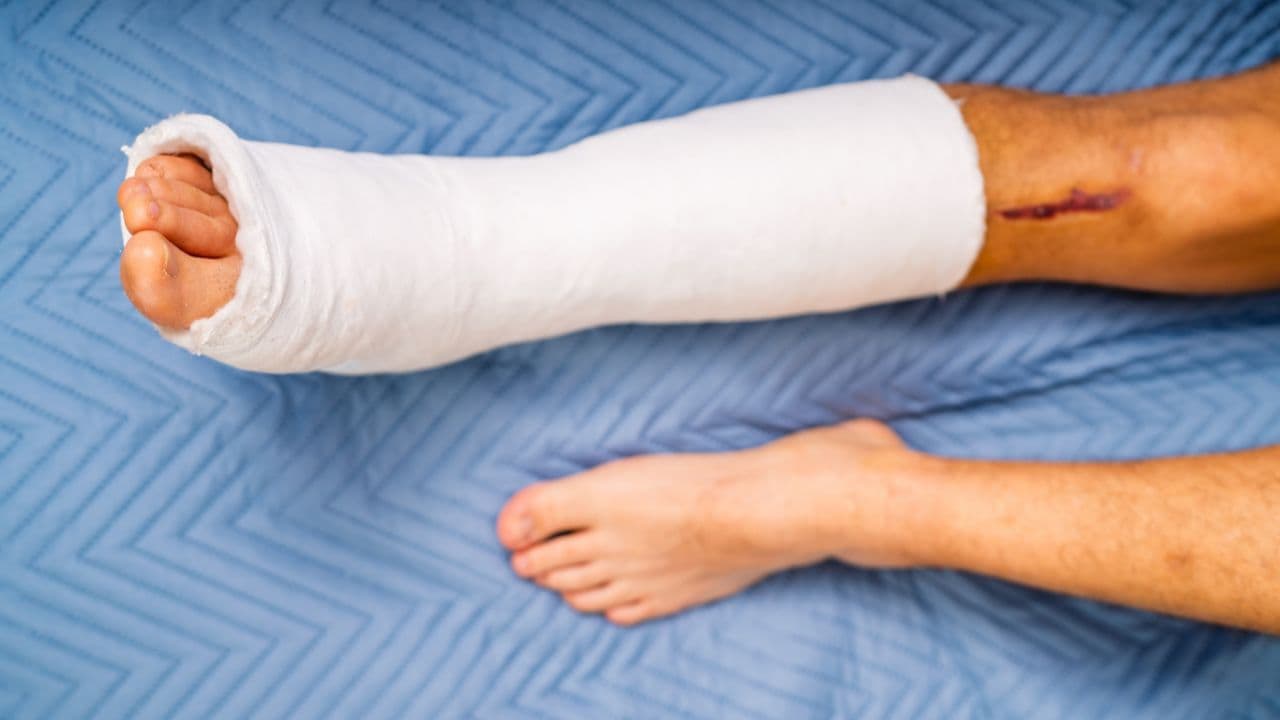

Quando falamos em sequelas de fratura de tíbia e fíbula, estamos falando daquelas dificuldades que persistem meses ou anos após o acidente. Pode ser um tornozelo que não dobra tudo o que deveria, um joelho que estala e dói ao subir escadas ou até mesmo uma perna que ficou um pouquinho mais curta que a outra, causando desequilíbrio na coluna.

Para um trabalhador braçal, como um pedreiro ou um motorista, ter sequelas de fratura de tíbia e fíbula significa perder produtividade. Você demora mais para fazer o serviço, cansa mais rápido e, às vezes, não consegue mais carregar o mesmo peso de antes. É justamente para compensar essa perda que a lei previdenciária existe.